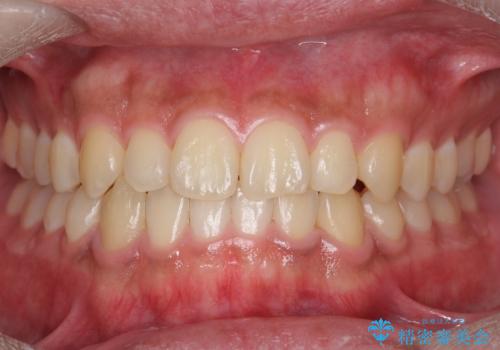

[ マウスピース矯正 ] がたがたした歯並びを治したい

担当医 大元洋佑

![[ マウスピース矯正 ] がたがたした歯並びを治したいの症例 治療前](https://seimitsushinbi.jp/wp/wp-content/uploads/2024/04/IMG_0106-500x350.jpg?v=1711951424)

![[ マウスピース矯正 ] がたがたした歯並びを治したいの症例 治療後](https://seimitsushinbi.jp/wp/wp-content/uploads/2024/04/46939b7482334672d3a091da1562afec-500x350.jpg?v=1711951403)